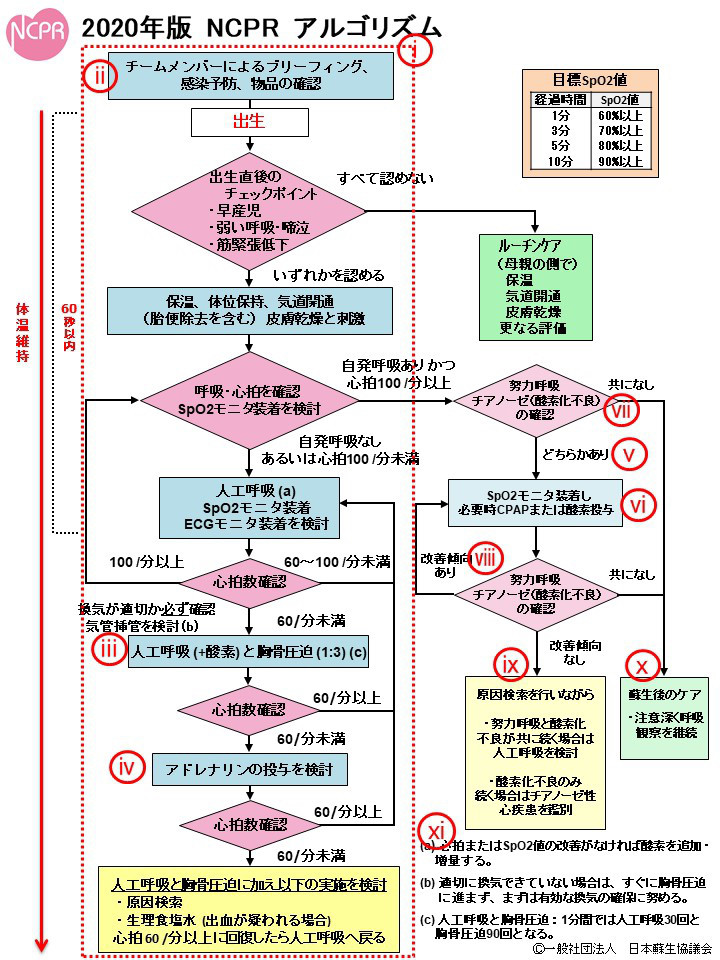

外傷の評価として基本的には「ABCD」を評価

A(Airway):気道

B(Breathing):呼吸

C(Circulation):循環

D(Dysfunction of central nervous system):中枢神経機能異常

今回のように出血が死因につながるような状況では

MARCHという考え方の評価

M(Massive hemorrhage):大量出血

A(Airway):気道

R(Respiratory):呼吸

C(Circulation):循環

H(Hypothermia):低体温、Head injury(頭部外傷)の評価